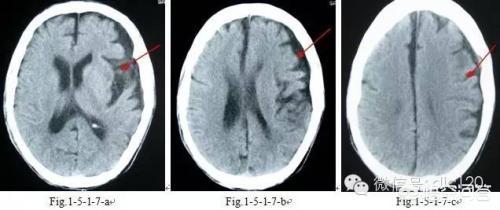

3, le processus de formation de la sténose vasculaire cérébrale est un processus chronique, la sténose vasculaire cérébrale est un processus chronique, la sténose vasculaire cérébrale est un processus chronique.Stades précoces de sténose (sténose légère)Il n'y a pas d'effet notable sur le flux sanguin lorsque le vaisseau atteint la région de larétrécissement modéréL'apport sanguin aux tissus situés plus loin de la sténose est partiellement réduit, mais l'organisme peut encore le tolérer. Lorsque le tissu cérébral se trouve dans la phase de compensation d'une ischémie légère, le risque d'infarctus cérébral est plusieurs fois plus élevé que chez les personnes normales. Au cours de cette période, l'infarctus cérébral peut survenir dans diverses conditions susceptibles d'entraîner une hypoperfusion du flux sanguin cérébral, telles queHypotension, perte de sang et anémieetc. En cas de rétrécissement important des vaisseaux sanguins cérébraux, comme indiqué précédemment, un infarctus cérébral peut survenir à tout moment. S'il s'agit d'un problème d'occlusion de gros vaisseaux sanguins, le problème est grave et peut faire l'objet d'un traitement chirurgical ; s'il s'agit d'un problème de petits vaisseaux sanguins à l'extrémité distale des vaisseaux sanguins, le problème est grave.Il s'agit d'un infarctus cérébral lacunaire, appelé infarctus lacunaire.La répartition des vaisseaux sanguins dans le crâne ressemble à celle d'un grand arbre. Le tronc principal de l'arbre est constitué par les gros vaisseaux sanguins, qui se ramifient continuellement vers l'extrémité distale. Il en va de même pour le tissu cérébral : plus les vaisseaux sanguins sont distaux, plus ils sont petits et plus la zone de tissu cérébral qu'ils alimentent est petite. Ainsi, lorsque ces petits vaisseaux sanguins se dérèglent, ils provoquent un infarctus cérébral lacunaire.

- Toutefois, outre les différences de présentation clinique, il arrive parfois que l'on ne soit pas en mesure d'évaluer l'efficacité du traitement.Le diagnostic ne peut pas être établi uniquement sur la base des symptômes cliniques.Les résultats doivent également être obtenus à l'aide de tests d'imagerie, tels queCT crânien et IRM crânienne. Qu'il s'agisse d'un infarctus lacunaire ou d'un infarctus cérébral, il n'y a pas de changement significatif au scanner crânien dans les 24 heures car le tissu cérébral est seulement ischémique et hypoxique, et il n'y a pas de nécrose liquéfiée du tissu cérébral infarci. Il est possible de l'identifier dans une certaine mesure lorsqu'il date de moins de 24 heures. Dans la phase aiguë des symptômes, l'IRM crânienne est le premier choix d'examen en clinique. Il existe différentes séquences d'IRM, et différentes séquences d'IRM peuvent être utilisées pour réaliser des examens pertinents pour différents cas.Pour le diagnostic de l'infarctus cérébral, les séquences DWI peuvent être très intuitives pour clarifier la situation.。

(3) Examen : tomodensitométrie ou examen magnétique nucléaire de la tête, le meilleur étant l'examen magnétique nucléaire, qui permet de trouver des foyers caverneux dans les parties correspondantes du cerveau.

Le diagnostic d'infarctus cérébral et d'infarctus cérébral lacunaire doit être précisé par un scanner ou une IRM cérébrale, car l'hémorragie cérébrale et l'infarctus cérébral ont les mêmes manifestations et il n'est pas possible de juger sur la base des manifestations.